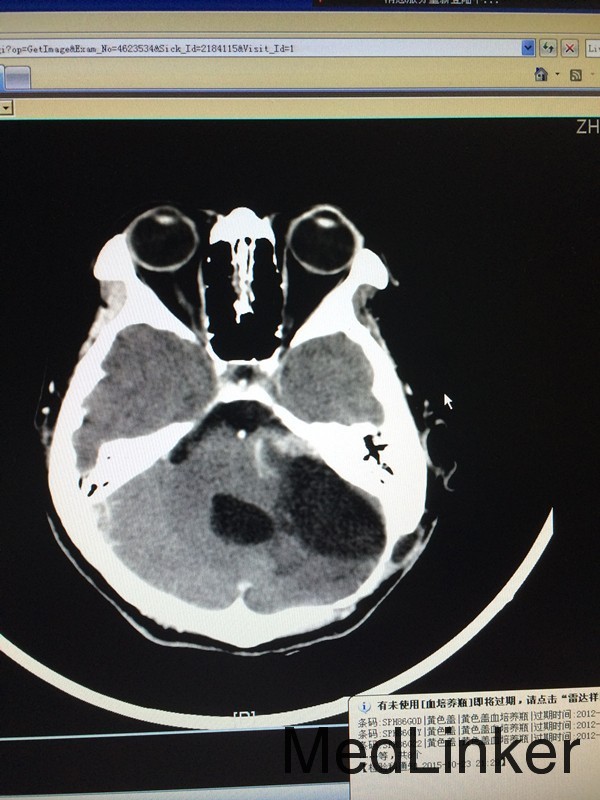

查体:左侧轻微面瘫,左侧面部感觉稍减退,余无特殊 辅助检查:头颅CT提示左侧桥小脑角区类圆形肿物,考虑听神经瘤可能,四脑室受压变窄并右移

诊断:左侧听神经瘤 治疗:行左侧桥小脑角区占位切除术,术后病理提示左侧桥小脑角神经鞘瘤